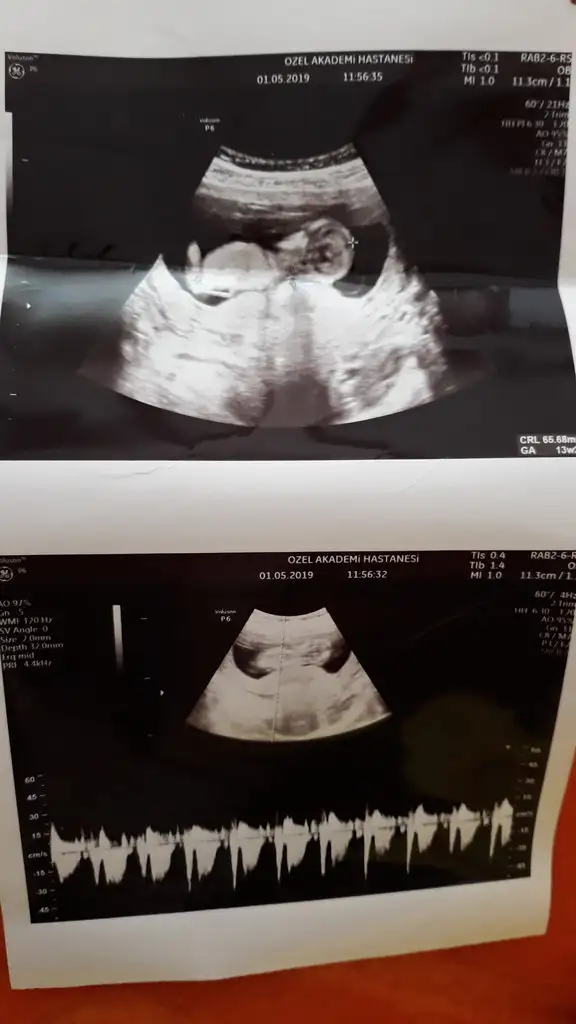

canım gözün aydın maşallah sevindim senin adına :) kız gibi dediyse kızdır çünkü 13+2 kocaman olmuş:)Kızlar ancak fırsat buldum yazmaya

Kontrolden çıktık sata gore 12+4 ultrasona gore geriden gelen bebişim bugun 13+2 cikti :) boyu 6.5 cm olmuş ense ve burun kemiğine iyi dedi kac diye sorunca 1den kucuk merak etme sorun yok dedi doktorumkan verdim 1 hafta sonra çıkacakmış sonuç doktorum cinsiyetle ilgili de kıza benziyor ama kesin değil dedi ve ben basından beri kiz hissediyorum:) en son gittiğimde mercimek tanesi kadardı ama bugun gercekten bir bebek gordum zıplayan kayan ellerini oynatan, Rabbimin gerçekten bir mucizesi Allahım hepimize boyle guzel haberler almayi nasip etsin inşallah tekrar :)Eki Görüntüle 2264270 Eki Görüntüle 2264272 Eki Görüntüle 2264270 Eki Görüntüle 2264272